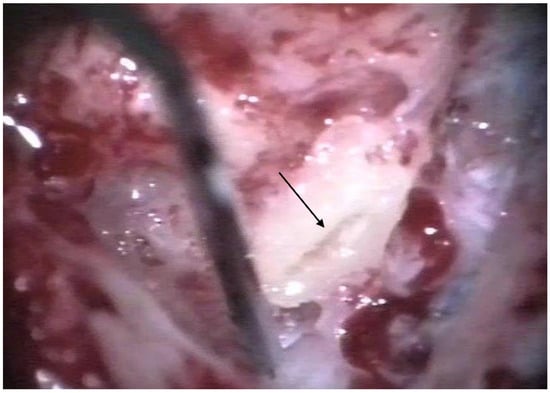

The patients were treated between August 2013 and October 2015 using the identical surgical technique of one-stage cochlear implantation and the occlusion of all three ipsilateral semi-circular canals. For cochlear implantation, a posterior tympanotomy and a round window approach were chosen [14]. Occlusion of the three semi-circular canals was performed before the implantation by reducing the drill speed to 10,000/min. The labyrinth was skeletonized to identify all semi-circular canals. The superior bony layer of the semi-circular canal was drilled down with a diamond burr (2.3 mm) until the endolymphatic duct shone through the last bony layer (blue lining) (Figure 1 and Figure 2). Leaving the endolymphatic duct intact, the temporalis fascia was pushed down in the canal. After sealing with fascia, the canal was filled with bone wax (Figure 3). The area of each canal was covered afterward with a muscle patch and bone pate. Finally, the sealing patch was secured with fibrin glue (Figure 4) [5,15].

Figure 1. Blue lining of the lateral semi-circular canal with the diamond burr. The arrow points to the lateral semi-circular canal.

Figure 2. After blue lining of the lateral semi-circular canal, the canal was filled with fascia. The arrow points to the lateral semi-circular canal.